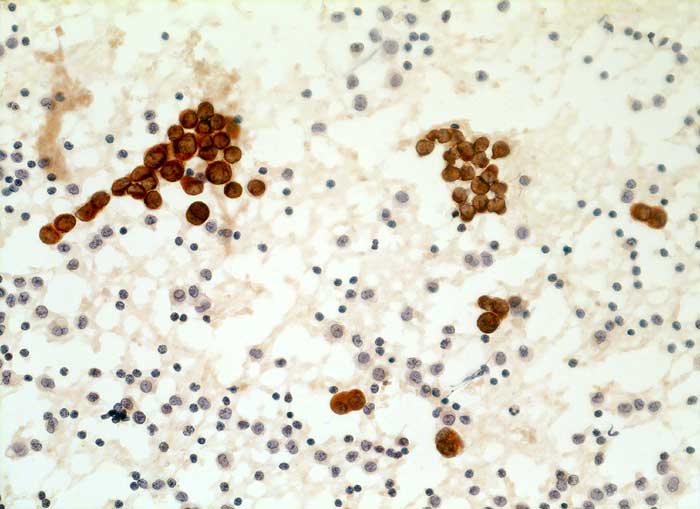

Aszitespunktat: Die Mesothelzellen sind positiv für den Panzytokeratinmarker Lu-5. Die Entzündungszellen sind Lu-5 negativ.

Immunzytochemisch reagieren erwartungsgemäss die Mesothelien

deutlich mit dem panepithelialen Antikörper Lu-5. Mit dem

epithelialen Marker Ber-EP4 stellen sich jedoch keine Zellen dar.

Dies spricht gegen das Vorliegen eines Karzinoms.

Zytologische Diagnose: Keine Malignität

Kommentar: Leicht abnorme Mesothelverbände oder Makrophagenaggregate sind typisch für Ergüsse bei Lebererkrankung. Die Differentialdiangose gegenüber einem Karzinom ist manchmal schwierig. Da BerEp-4 in ca. 90% aller Karzinome positiv ist, Mesothelien aber nicht mit dem Marker reagieren, ist dieser Marker eine wertvolle Hilfe. Die Mesothelzellverbände sind dagegen für Lu-5 und polyklonales Keratin positiv und nicht zur Differenzierung von Mesothelien und Karzinomzellen geeignet.

Kommentar: Leicht abnorme Mesothelverbände oder Makrophagenaggregate sind typisch für Ergüsse bei Lebererkrankung. Die Differentialdiangose gegenüber einem Karzinom ist manchmal schwierig. Da BerEp-4 in ca. 90% aller Karzinome positiv ist, Mesothelien aber nicht mit dem Marker reagieren, ist dieser Marker eine wertvolle Hilfe. Die Mesothelzellverbände sind dagegen für Lu-5 und polyklonales Keratin positiv und nicht zur Differenzierung von Mesothelien und Karzinomzellen geeignet.